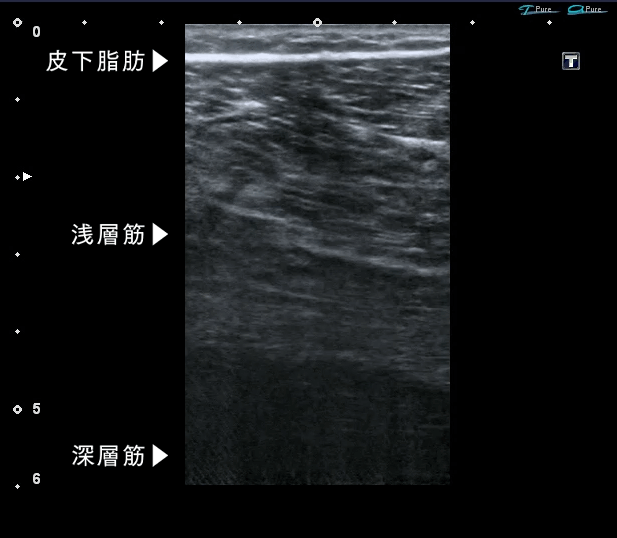

深層筋まで

刺激する

独自のEMS搭載

届くEMSが

足を強くする。

※太ももに使用。約6㎝の深さの筋肉まで刺激が十分に到達すること。

POINT1

深層筋まで届くEMSが

約6cmまで届くパワフルな電気刺激が、筋肉を効率的に収縮させ鍛えます。ランダムに変化する独自の周波数が筋肉を慣れさせず、効率的なトレーニングをサポートします。